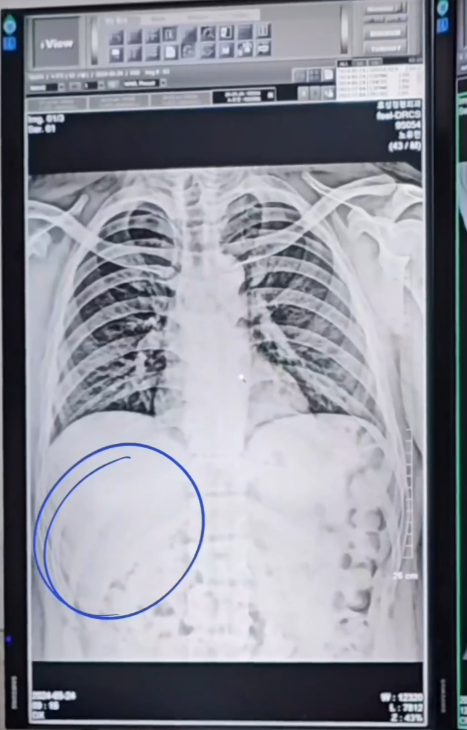

이어 "옥상 방수 작업을 하려고 재료와 장비를 실어 올리는 리프트에 노대표(노유민) 손목이 껴서 잘릴 뻔"이라며 "병원가서 사진 찍어보니 다행히 뼈는 괜찮았다"고 당시 상황을 전해 충격을 안겼다.

그러면서 "오히려 갈비뼈 통증이 심해서 약물치료하며 조금씩 나아지고 있다. 별 거 아닌 일에도 항상 주의를 기울이고 다치지 않도록 늘 조심하시길 바란다"며 주의를 당부했다.

노유민은 해당 글과 함께 영상 한 개를 공개했는데, 공개된 영상 속에는 리프트 끼임 사고로 생긴 흉터, 갈비뼈 엑스레이 사진 등이 담겼다.

병원가서 사진찍어보니 다행히 뼈는 괜찮았고 오히려 갈비뼈 통증이 심해서 약물치료하며 조금씩 나아지고 있어요.